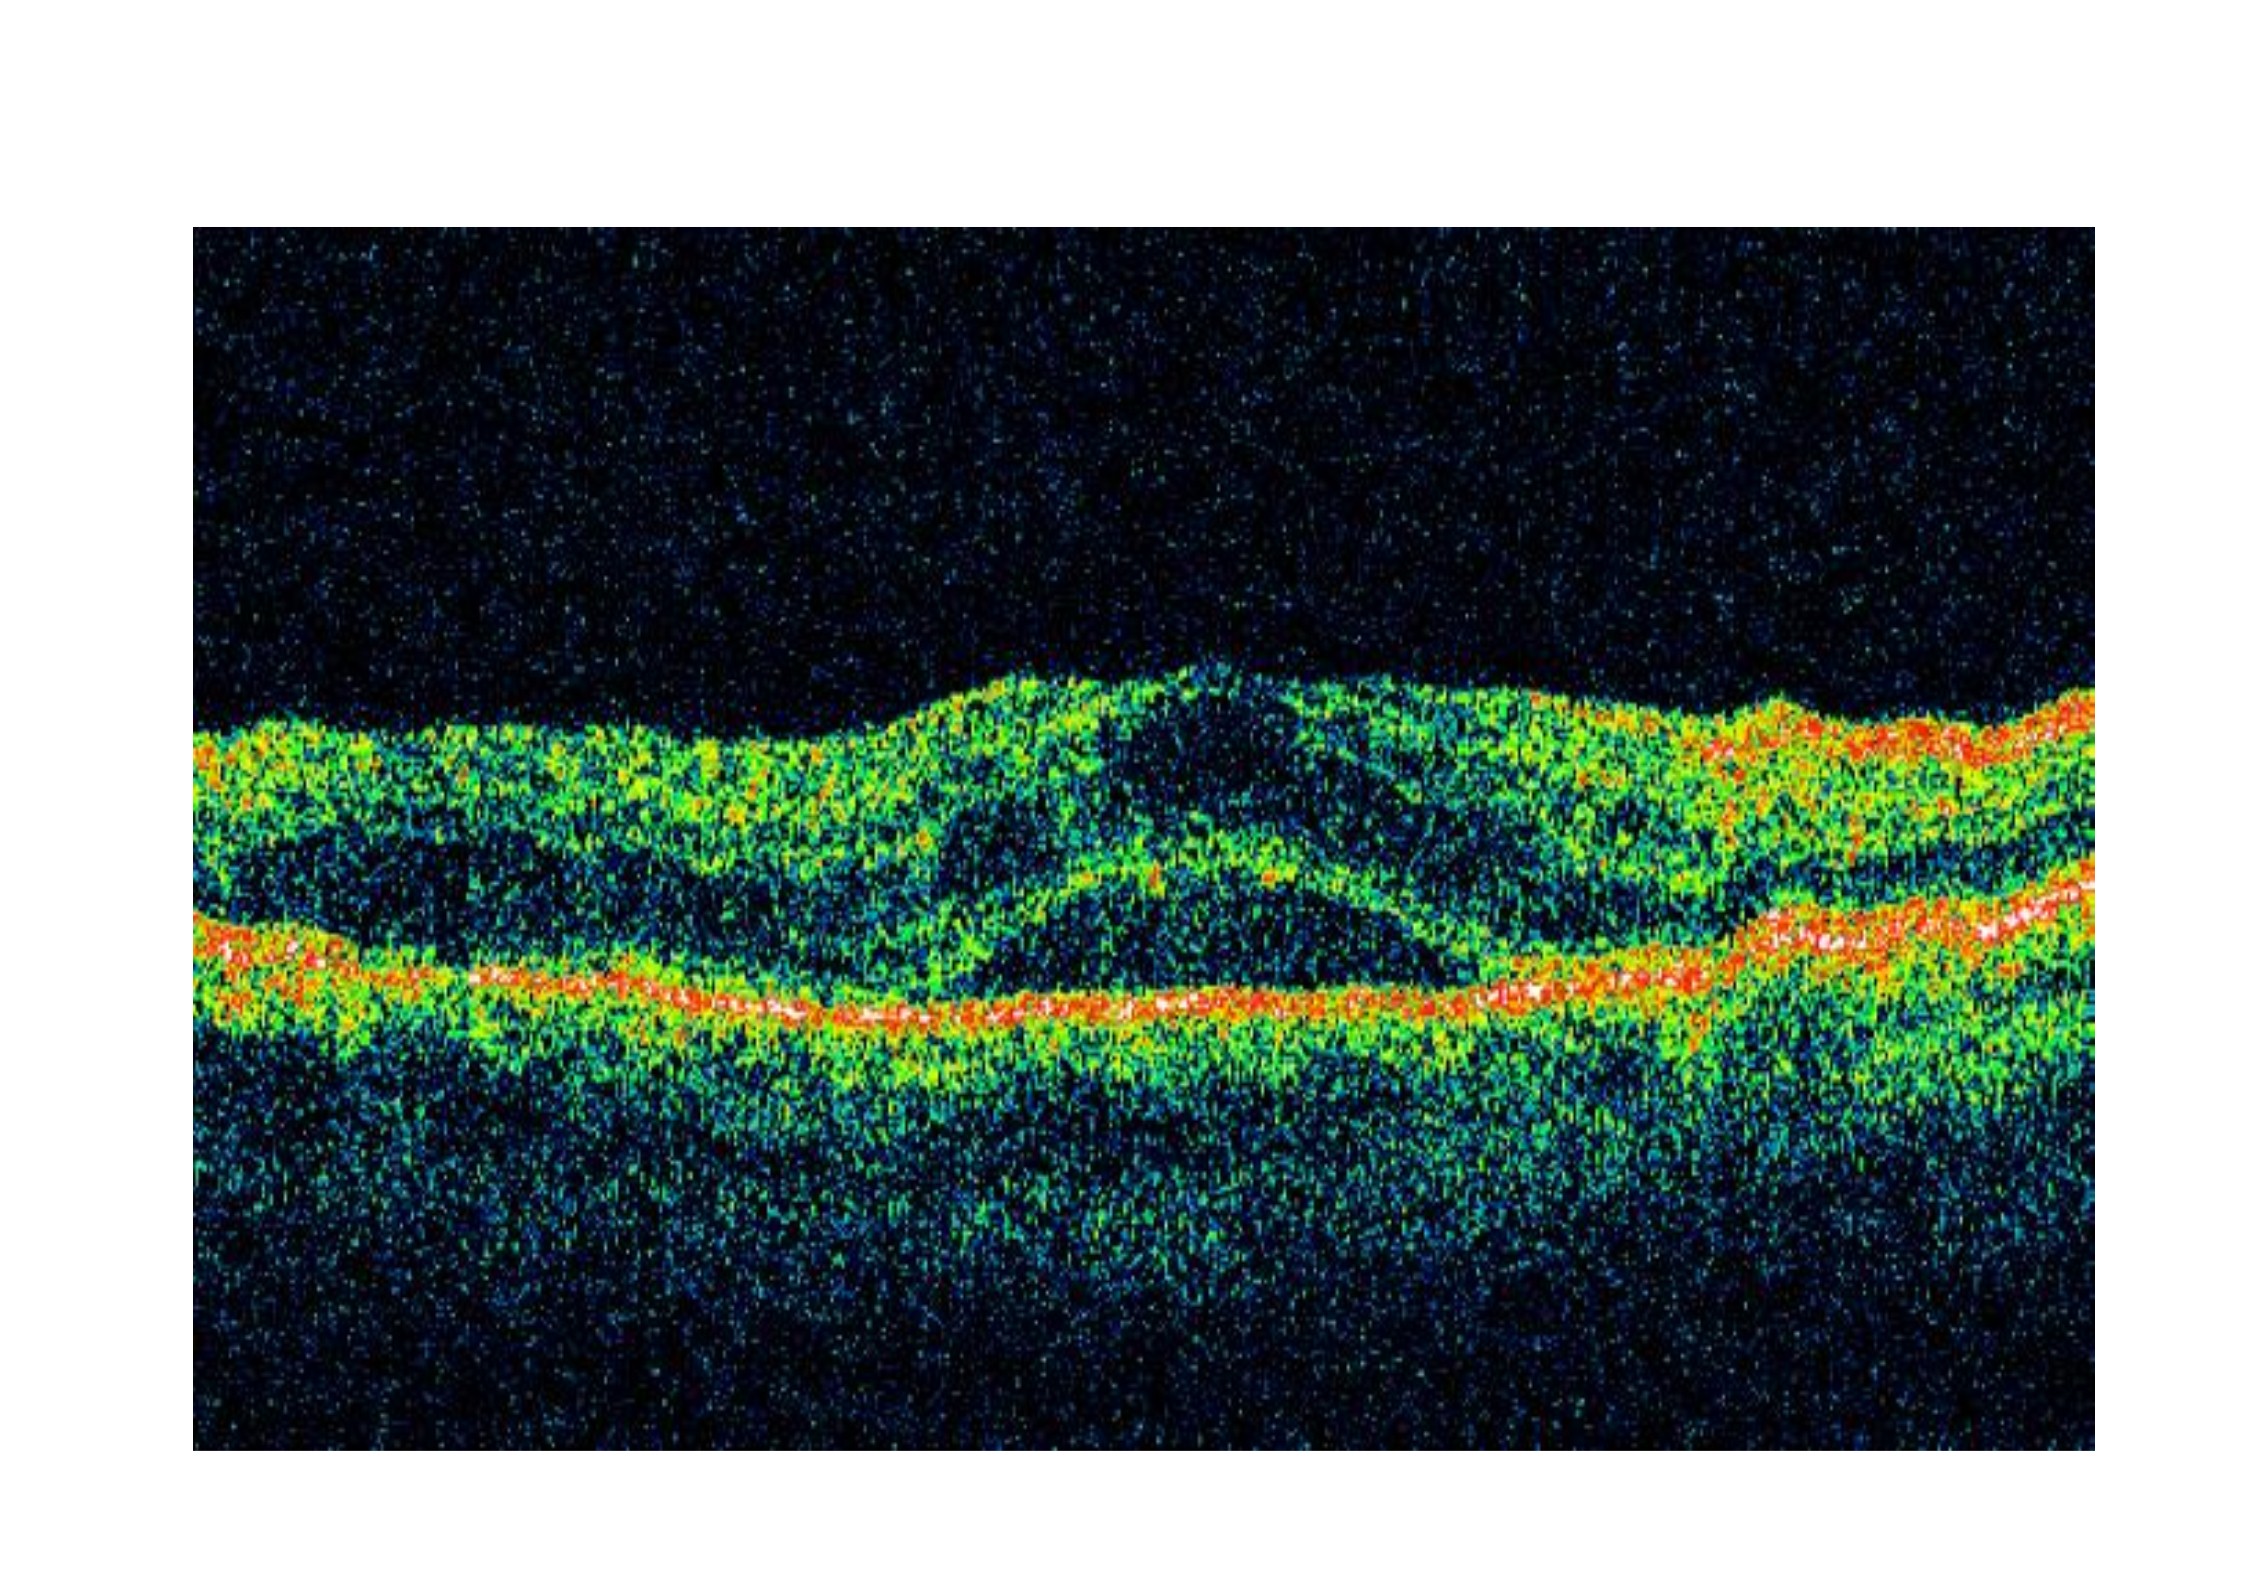

En este estudio, 66 pacientes con edema macular diabético recibieron una fase de carga de 3 inyecciones de ranibizumab mensual , y después fueron asignados a recibir tratamiento combinado con terapia láser más ranibizumab (n=34 ) o monoterapia con ranibizumab (n=32). En ambos grupos , el espesor central de la retina se redujo significativamente desde el inicio y la agudeza visual mejoró significativamente. No hubo diferencia significativa entre los 2 grupos en el espesor central de la retina o de la agudeza visual aunque en el grupo combinado se observó una tendencia a una mejor agudeza visual, con una mejoría de más de 15 letras en el 21% de los casos. El 65 % del grupo de tratamiento combinado no necesitó un nuevo tratamiento durante 1 año, en comparación con solo el 16 % del grupo de monoterapia.